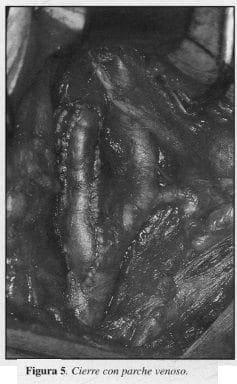

6. Cierre de la arteriotomía: directa (Figura 4) 15 casos (65.1%); parche venoso (Figura 5), 3 casos (13,6%); parche artificial (Dacrón o Teflón), 4 casos (18,18%).